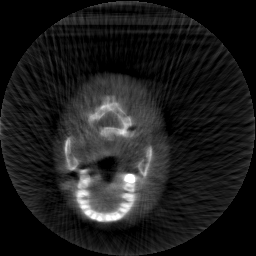

Krylov subspace methods are a powerful family of iterative solvers for linear systems of equations, which are commonly used for inverse problems due to their intrinsic regularization properties. Moreover, these methods are naturally suited to solve large-scale problems, as they only require matrix-vector products with the system matrix (and its adjoint) to compute approximate solutions, and they display a very fast convergence. Even if this class of methods has been widely researched and studied in the numerical linear algebra community, its use in applied medical physics and applied engineering is still very limited. e.g. in realistic large-scale Computed Tomography (CT) problems, and more specifically in Cone Beam CT (CBCT). This work attempts to breach this gap by providing a general framework for the most relevant Krylov subspace methods applied to 3D CT problems, including the most well-known Krylov solvers for non-square systems (CGLS, LSQR, LSMR), possibly in combination with Tikhonov regularization, and methods that incorporate total variation (TV) regularization. This is provided within an open source framework: the Tomographic Iterative GPU-based Reconstruction (TIGRE) toolbox, with the idea of promoting accessibility and reproducibility of the results for the algorithms presented. Finally, numerical results in synthetic and real-world 3D CT applications (medical CBCT and {\mu}-CT datasets) are provided to showcase and compare the different Krylov subspace methods presented in the paper, as well as their suitability for different kinds of problems.